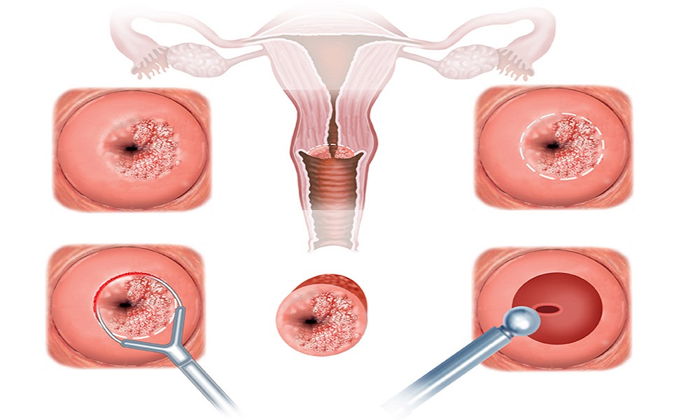

Genellikle adet gecikmesi olan hanımlar ya koşup eczanede satılan gebelik testlerinden bir tane alıp kendi kendilerine test yaparak ya da bir hastaneye veya bir laboratuvara gidip kan testi yaptırarak gebeliklerini öğrenirler. İşte bundan sonra çok fazla vakit kaybetmeden bize başvurmaları gerekir. Çünkü gebeliğin başlangıcında yapılması gereken en önemli şey vajinal ultrasondur. Vajina yoluyla yapılan erken gebelik ultrasonu oluşan gebeliğin normal yerinde yani rahim yani uterus içinde olup olmadığını ve gebelik eğer normal yerinde ise sağlıklı görünüp görünmediğini, herhangi bir düşük riskinin olup olmadığını anlamaya, eğer normal yerinde değilse servikal yerleşimli bir gebelik olup olmadığı, Ektopik yani Dış Gebelik olup olmadığını, Dış Gebelik ise hangi safhada olduğunu,dış Gebeliğin bir Cerrahi operasyon gerektirip gerektirmediğini ya da ilaçla tedavi edilecek durumda olup olmadığını tespit etmeye yarayan ALTIN DEĞERİNDE BİR TANI ARACIDIR.

Gebeliğin ilk 12 haftasında Vajinal Ultrason yapılmalı ve Gebeliğin sağlıkla gidişatı en yakın şekilde takip edilmelidir. Halk arasındaki YANLIŞ inanışın tersine Vajinadan yapılan Ultrason ve muayene gebeliğe bir zarar vermez.

Doğum şeklini belirlemek için son haftalarda bebeğin geliş pozisyonu, anne adayının çatısının durumu vajinadan yapılan özel bir muayene ile tespit edilir. Her zaman doğumda ilk tercihimiz Normal Vajinal Doğumdur. Ancak gerekli koşullar sağlanamadığında ikinci tercihimiz olan Sezaryen’e yöneliriz.